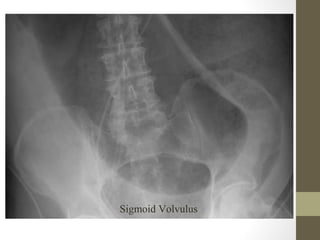

Radiographic Studies

• Plain film: abdominal x-ray, chest x-ray

Radiographic Studies: Plain

Film

• Mostly helpful in ED for:

– Free air (suspected perforation)

– Pneumatosis (typhlitis)

– Dilated loops of bowel with air fluid levels (obstruction)

– Foreign body

• Free air seen in only 30-50% of bowel perforation

Sigmoid Volvulus

What’s wrong with this picture?

Radiographic Studies: Plain Film •Mostly helpful in ED for: – Free air (suspected perforation) – Pneumatosis (typhlitis) – Dilated loops of bowel with air fluid levels (obstruction) – Foreign body • Free air seen in only 30-50% of bowel perforation

• 31.

• 32.

• 33.

What’s wrong withthis picture?